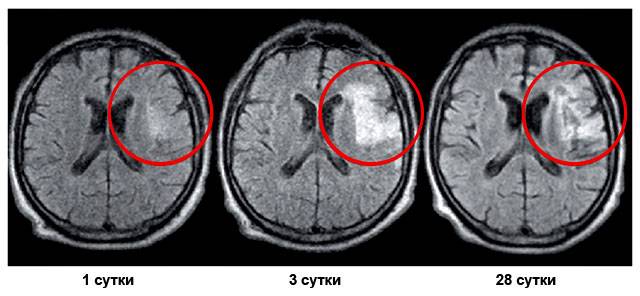

Небольшие размеры омертвевшего участка мозга

Если по данным томографии специалисты не классифицируют ишемический инсульт как массивный (большой) или говорят о нем как о микроинсульте, это значит, что прогноз для жизни больного благоприятный. Такие изменения в головном мозге не оказывают существенного влияния на ее продолжительность – болезнь не смертельная. Исключение составляют случаи, при которых нарушено кровоснабжение ствола мозга. В нем расположены жизненно важные центры – дыхательный и сердечно-сосудистый. Поэтому даже небольшой инсульт, затрагивающий ствол головного мозга, в 95–99% заканчивается смертью больных в течение нескольких часов или дней.

Любые последствия ишемического инсульта склонны уменьшаться со временем (до 1–1,5 лет), если проводится полноценное восстановительное лечение и реабилитация.

Сколько утраченных функций восстановил больной за 1–2 года, такими будут его способности до конца жизни. Это значит, что по происшествии этого времени нервные клетки практически не восстанавливаются и имеющиеся изменения мозга становятся необратимыми.

Массивный очаг

Если по данным томографии участок инфаркта (омертвения) головного мозга расценивается, как большой (массивный инсульт), прогноз неблагоприятный. Такие больные либо умирают в течение нескольких дней (60–70%), либо выживают, становясь глубокими инвалидами (30–40%).